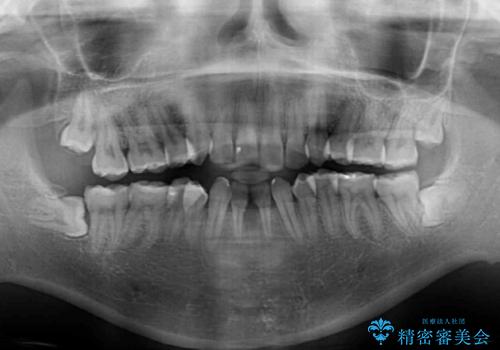

後戻りの再矯正 ワイヤー装置でデコボコと隙間を改善

- 学生時代の抜歯矯正の後戻りが気になり、再矯正を希望して来院された患者様です。

マウスピース矯正は継続する自信がなく、気になるところを短期間で改善したいとのことで、ワイヤー装置にて矯正治療を行うこととしました。

詰め物で隠していた下顎前歯の隙間は、歯軸を改善することで詰め物を除去しても隙間が目立たなくなりました。

まだ改善したいところはありましたが、患者様自身は大変満足されたとのことで、治療を終えることとなりました。